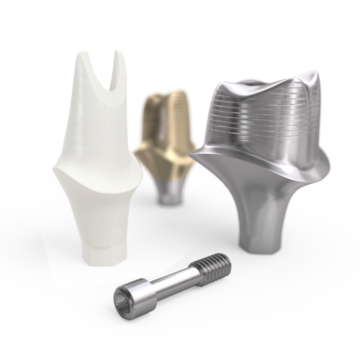

Conical Seal Design – a strong and stable fit

A conical connection that seals off the interior of the implant

from surrounding tissues, minimizing micromovements and microleakage.

Connective Contour – increased soft tissue contact zone and volume

The unique contour that is created when you connect the abutment to the implant.